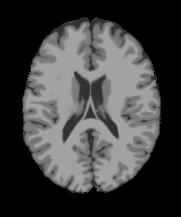

Magnetic Resonance Imaging (MRI) is a critical and widely used medical modality due to its noninvasive nature and ability to produce high-quality images of human organs and tissues. Segmentation in MRI refers to the process of dividing the acquired image data into specific tissues or regions of interest (ROIs). In the context of brain slice MRI data, this often involves distinguishing between cerebrospinal fluid (CSF), gray matter (GM), and white matter (WM), in 2D image slices as depicted in Fig. 1. Research topics on brain anatomy and functionality (e.g., Alzheimer’s disease, tumor detection, neurodegenerative processes, etc.) demand reliable segmentation tools since their outcomes directly impact the subsequent analysis of the brain slice MRI. Therefore, the development of any accurate MRI segmentation framework has to deal with the following issues:

(1) where can be interpreted as a smoother version of . With a little abuse of notation, we indicate the equation (1) as a cartoon-texture (CT) decomposition (even though we do not aim to compute a proper CT decomposition), where is the ‘cartoon’ depicting the structural component, and the ‘texture’ part including oscillatory components, like texture and noise, as shown in Figure 1.

Figure 3 illustrates the workflow of the algorithm SegMIC2T using the slice060 with low (top row) and moderate (bottom row) levels of the combined artifacts. The noise estimation step splits the original MRI slice into a cartoon image (second column) and a texture image (third column) (1). The correction step, coinciding with the application of the proposed multiaffine ADMM method, produces a denoised and debiased version of the original slice, whose th pixel corresponds to (fourth column). In the last step, the segmentation of the original slice is produced by clustering the pixels in the corrected image (fifth column).